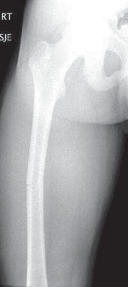

Chapter 13 Flexible Intramedullary Nailing of Femoral Shaft Fractures Gilbert Chan and John M. Flynn DEFINITI…

Chapter 12 Closed Reduction and External Fixation of Femoral Shaft Fractures Stuart M. Myers and John M. Flyn…